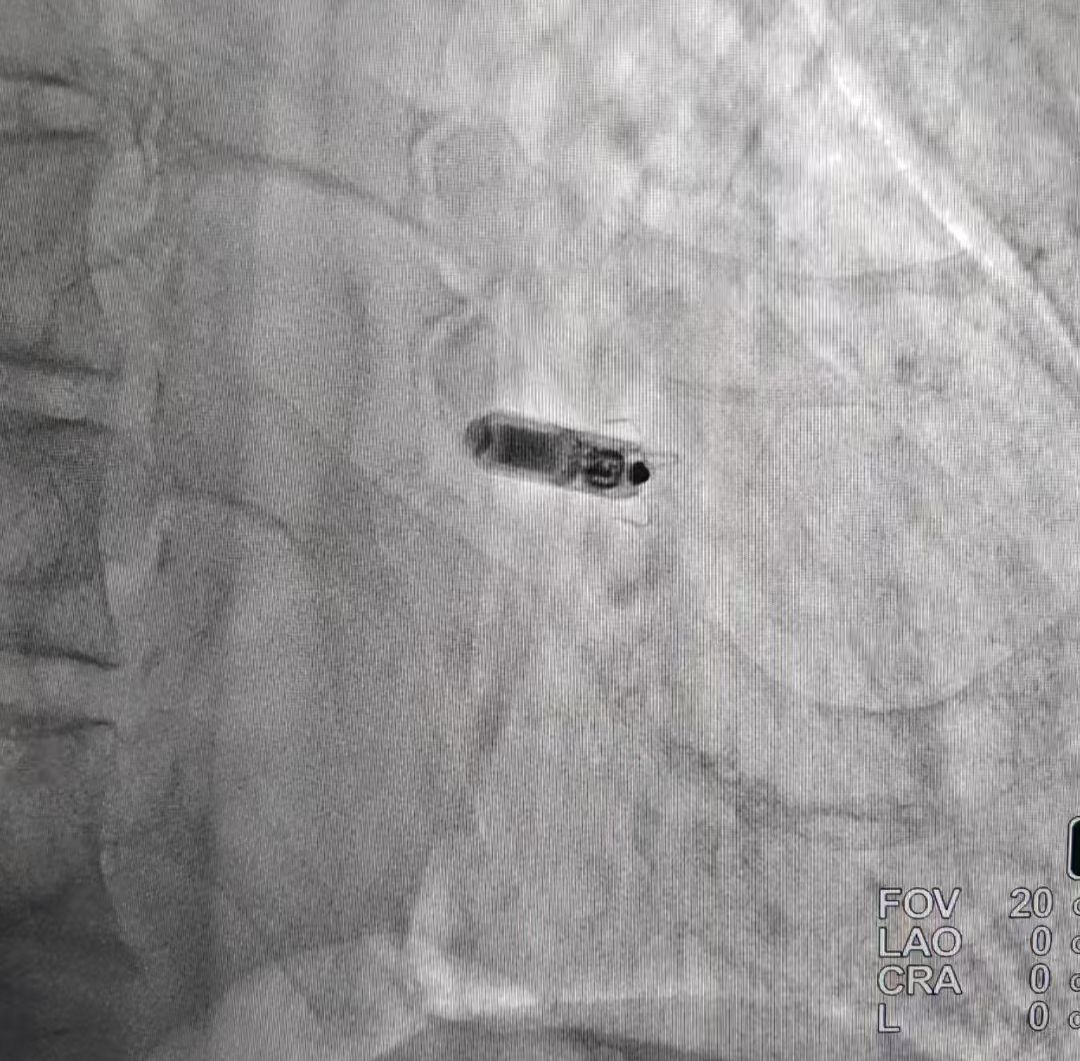

医生经讨论决定采用新型无导线起搏器 (Micra) 救治患者。术中医生穿刺右侧股静脉,经鞘管输送 Micra 无导线起搏器顺利至右室中位间隔区域,测试心室起搏阈值 0.5V,阻抗 920Ω,感知 8.6mV,参数良好满意。术后患者活动后乏力气短等症状明显改善。